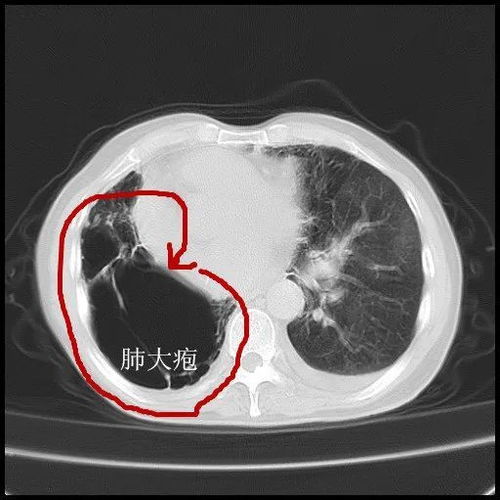

要看嚴(yán)重度。無(wú)癥狀的肺大皰不需治療,一般是加強(qiáng)營(yíng)養(yǎng)、多運(yùn)動(dòng)、休息好保持心情舒暢、避免寒冷刺激,當(dāng)然如果肺大炮較多且較大,則避免用力吹氣,比如不做肺功能檢查,避免肺部感染。伴有慢性支氣管炎或肺氣腫的患者,主要治療原發(fā)病變.繼發(fā)感染時(shí),應(yīng)用抗生素.肺大皰體積大,占據(jù)一側(cè)胸腔70%~100%,臨床上有癥狀,而肺部無(wú)其它病變的患者,手術(shù)切除肺大皰可以使受壓肺組織復(fù)張,呼吸面積增加,肺內(nèi)分流消失,動(dòng)脈血氧分壓提高,氣道阻力減低,通氣量增加,患者胸悶,氣短等呼吸困難癥狀可以改善.